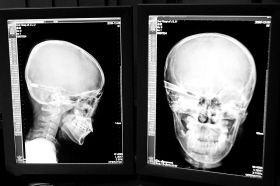

在接受x光檢查的小沖

“還是先做個(gè)X光透視,看一下箭桿到底有多深!毖劭漆t(yī)生緊急趕到CT室查看,和放射科的幾位醫(yī)生共同研究后,決定先讓小沖做X光透視。

“如果再用點(diǎn)力,就從后腦穿出來(lái)了!”由于小沖無(wú)法移動(dòng),醫(yī)生拿來(lái)移動(dòng)插座,將透視的光板放在小沖的移動(dòng)病床上,透視后讓在場(chǎng)的醫(yī)生都吃了一驚:箭桿直接穿過(guò)了大腦和小腦,箭尖兒直抵后顱骨,足足有10余厘米。